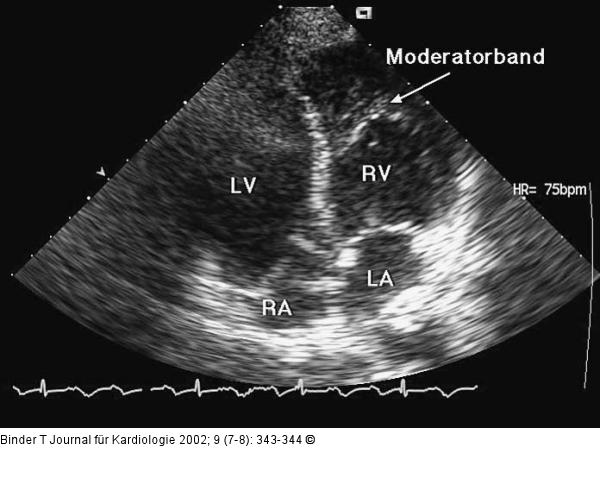

Abbildung 3: Kongenital korrigierte Transposition der großen Gefäße (ccTGA) Vierkammerblick: Das Vorhandensein eines Moderatorbandes (Muskelstrang, welcher quer durch den Ventrikel verläuft) und die starke Trabekulierung charakterisieren den rechten Ventrikel; LA = linker Vorhof; LV = (morphologisch) linker Ventrikel; RA = rechter Vorhof, RV = (morphologisch) rechter Ventrikel. |